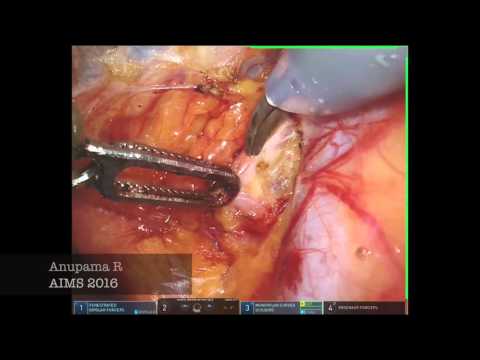

Humans of Robotic Surgery: Dr. Anupama Rajanbabu

Humans of Robotic Surgery, Surgeon ';